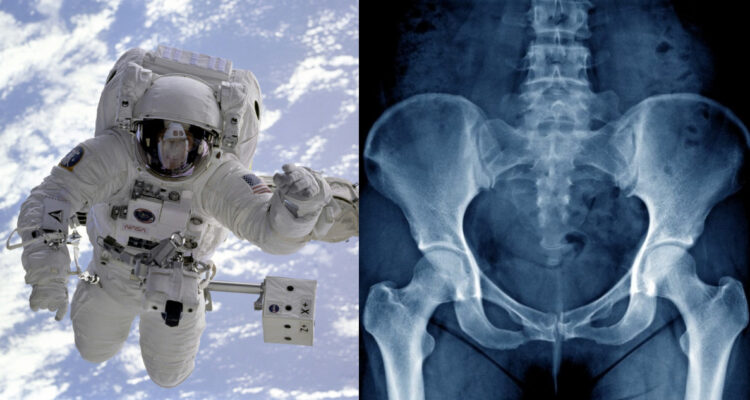

Se prevé que los primeros astronautas emprendan viajes espaciales hacia Marte para finales de esta década, sin embargo, este emocionante desafío conlleva serios riesgos para la salud ósea de los exploradores. La ingravidez del espacio provoca una acelerada osteoporosis al disminuir la actividad osteoblástica y aumentar la actividad osteoclástica, lo que se traduce en una rápida pérdida de masa ósea y alteraciones en su calidad. Estudios en astronautas de la Estación Espacial Internacional (EEI) revelan una alarmante pérdida mensual de densidad mineral ósea, lo que aumenta el riesgo de fracturas.

Ir a Marte puede resultar emocionante, pero tiene un lado oscuro: desencadena un proceso acelerado de osteoporosis. Someterse a la ingravidez produce indeseados efectos sobre el esqueleto y la pérdida de masa ósea.

De forma parecida, en un entorno de ingravidez, las cargas gravitatorias que normalmente actúan sobre los huesos disminuyen drásticamente. Esto implica que se produce la misma reducción en la actividad osteoblástica y el mismo un aumento en la actividad osteoclástica que estar inmovilizado en una silla de ruedas, con la consiguiente pérdida de la masa ósea, así como una alteración en su calidad, que aumenta el riesgo de fracturas.

Estudios realizados en astronautas que han pasado varios meses en la Estación Espacial Internacional (EEI) muestran una pérdida de DMO del 1-2 % mensual en las caderas y columna lumbar. Excesivamente rápida teniendo en cuenta que equivale a la pérdida que sufre en todo un año una persona de edad avanzada, sobre todo en las mujeres después de la menopausia.